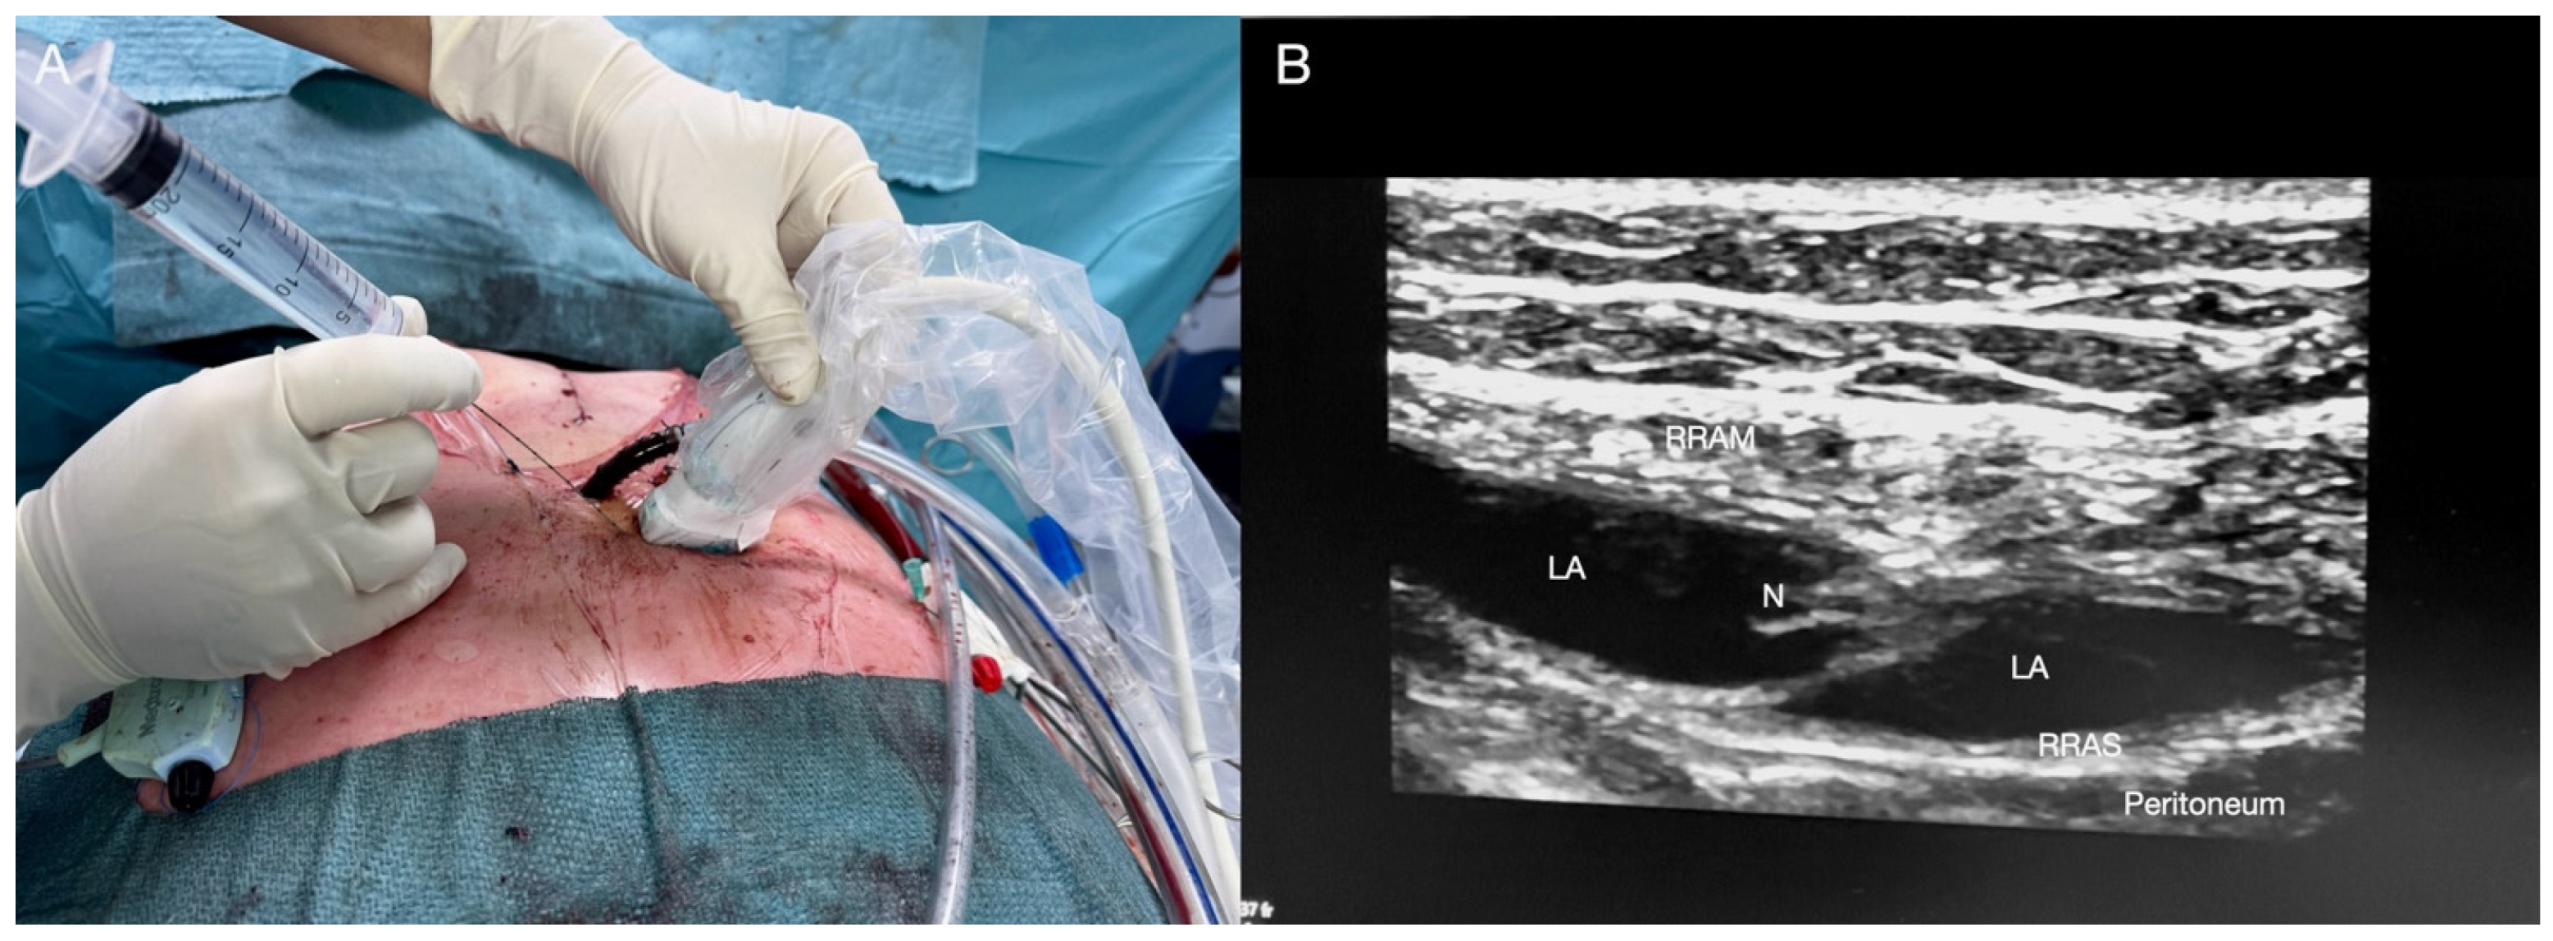

2.2. Rectus Sheath Block

Technique for RSB

| RSB | Postoperative subxiphoid drainages pain management. | T7 to T11 intercostal nerves, and subcostal nerve (T12). Posterior rectus muscle sheath. 10–15 mL of LA. | The LA is injected between the muscle and its posterior sheath, not between the two lines appearing as binary shaped. The “double V” sign (opening of two fascial planes) is not visible. Caution is needed to avoid inferior epigastric artery injury. |